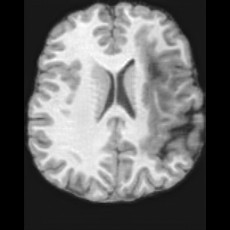

PathologicalHealthyDifferencew/o ACGw/ ACG(a)Refer to captionRefer to captionRefer to captionRefer to captionRefer to captionHealthyPathologicalDifferencew/o ACGw/ ACG(b)Refer to captionRefer to captionRefer to captionRefer to captionRefer to caption

Figure 6: Ablation study of Anatomy Consistency Guidance (ACG): (a) pathology-to-healthy; (b) healthy-to-pathology. Without ACG, edits cause anatomical inconsistencies outside lesions (arrows), whereas ACG keeps modifications lesion-focused.

Anomaly Consistency Guidance. Fig. 6 demonstrates the effectiveness of the proposed Anatomy Consistency Guidance (ACG) on bidirectional editing. Without ACG, the generated brains exhibit noticeable and unrealistic anatomical deformations in non-lesion regions (arrow-indicated), leading to structural inconsistencies between the edited and original brains, as shown in the corresponding difference maps. After incorporating ACG, the model effectively constrains editable modifications within pathological regions, while preserving the remaining anatomy. Tab. 4 further reports their quantitative performances: removing ACG leads to a substantial degradation in all L1, PSNR, and SSIM scores, reaffirming the critical role of ACG in achieving more accurate and structurally consistent reconstructions.